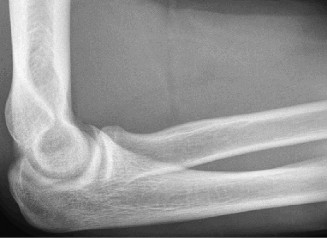

Rotator cuff tears are a common reason for shoulder pain and a common reason to obtain shoulder imaging. As a result, numerous different imaging modalities exist offering different pros and cons. Plain films are still the initial imaging modality of choice. These are most useful in ruling out other possible diagnosis but can help with the diagnosis of a rotator cuff tear as well. Changes to the tendon itself

may appear as calcific tendinosis, which would most commonly be seen at the bone–tendon interface. A decrease in the acromiohumeral distance (less than 2 mm) may also be indicative of a cuff tear. In late cases of rotator cuff tears, superior subluxation of the humerus may be evident. Certain variations in acromial anatomy, including spurs or a hook-shaped (type 3) acromions, may be associated with rotator cuff tears as well. With progression of rotator cuff tears, degenerative changes including spurs, cysts, and sclerosis may be evident at the greater tuberosity. In late, massive tears one may see degenerative changes consistent with rotator cuff arthropathy.